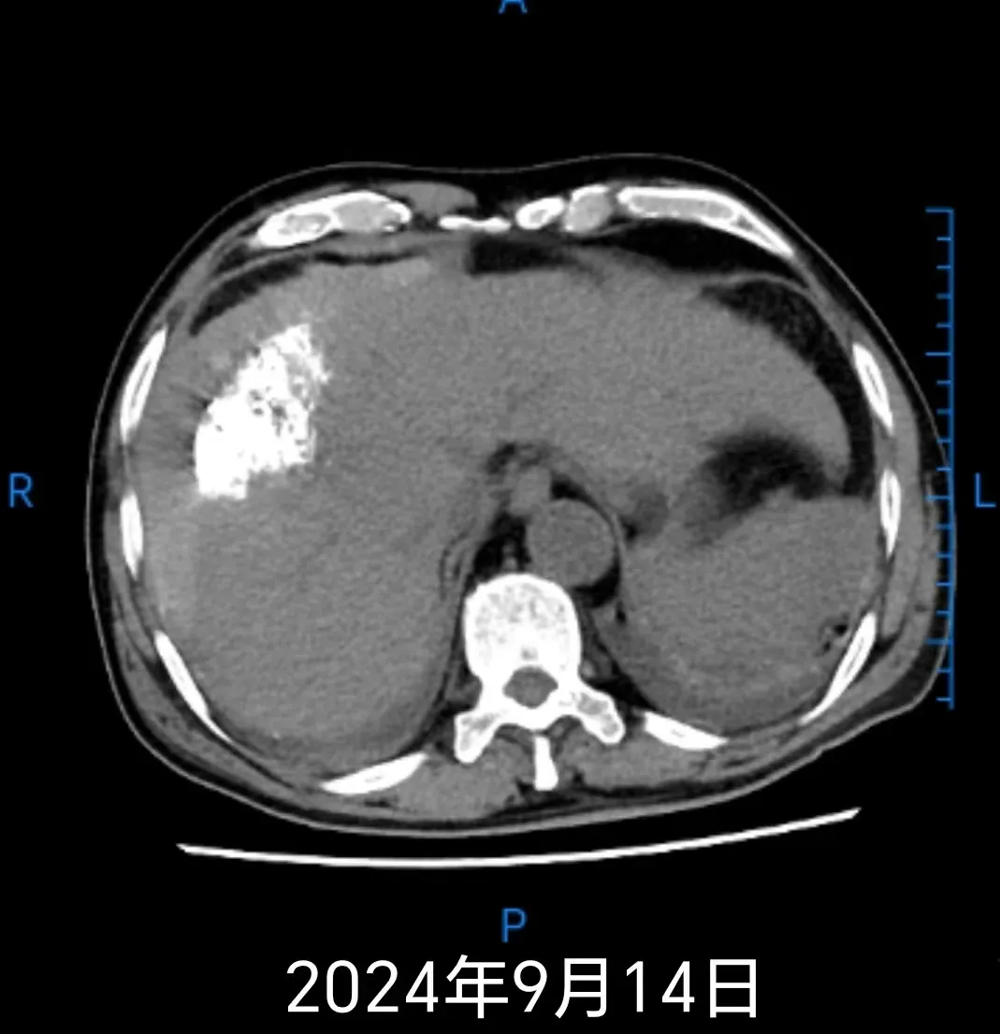

患者熊(xióng)某,男,67歲,因持續3小時(shí)腹痛於2024年(nián)9月11日23時30分就診於武寧縣人民醫院北院。急診CT檢查提示(shì):肝硬化,肝右(yòu)葉占位破裂出血(肝周、脾(pí)周積血)可能性大,左腎結石與血管鈣化待鑒(jiàn)別,盆腔積液。結合床旁彩超結果:肝內占位性病(bìng)變、肝右前間隙團絮狀稍(shāo)高回聲、腹腔中量積液,綜合考慮為(wéi)肝(gān)內占位性病變合並破裂出血。診斷為肝癌破裂出血、失血性休克,因病情危重,患者急診轉至人民醫院院區腫瘤消化科住院治療。

鑒於患者出血量大、生命體征不平穩,經與家(jiā)屬充分(fèn)溝通並簽署手術知情同意書後,於2024年9月12日03時急診在DSA下行經導管肝動脈栓塞術。術後患者(zhě)生命(mìng)體(tǐ)征平穩。9月14日(rì)複查CT顯示肝腫瘤及介(jiè)入術後改(gǎi)變,建議隨(suí)診複查或MRI檢查,同時提示腹盆腔積血。